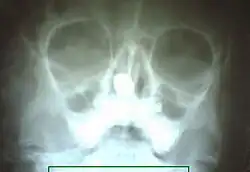

| X-ray of paranasal sinuses showing rhinolith | |

They may cause pressure necrosis of the nasal septum or lateral wall of nose. Rhinoliths can cause nasal obstruction, epistaxis, headache, sinusitis and epiphora. They can be diagnosed from the history with unilateral foul-smelling blood-stained nasal discharge or by anterior rhinoscopy. On probing, the probe can be passed around all its corners. In both CT and MRI a rhinolith will appear like a radiopaque irregular material. Small rhinoliths can be removed by a foreign body hook; large rhinoliths can be removed either by crushing with Luc's forceps or by Moore's lateral rhinotomy approach.[1][2]